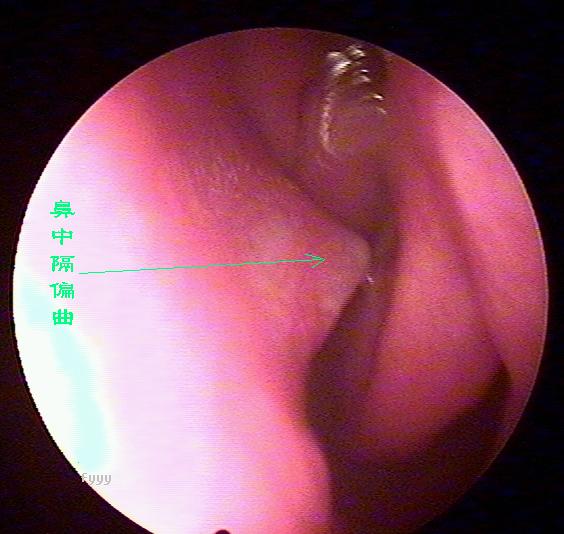

鼻内窥镜下的鼻中隔偏曲

老流鼻血可能是鼻中隔偏曲惹的祸,鼻中隔偏曲部位经常会出现血管畸形,而且这里的粘膜也相对较薄,受气流、尘埃等刺激后容易破损、出血,主要症状为:交替性或持续性鼻塞,头痛,鼻出血及流脓涕等。且难以痊愈,经常发作。西安新城中大耳鼻喉医院耳鼻喉科推出的微创手术,快速无痛治疗鼻中隔偏曲。

2、鼻出血:鼻出血是鼻中隔偏曲较为常见的症状之一。发生在偏曲之凸面、骨棘或骨嵴的顶尖部,此处粘膜薄。常受气流和尘埃刺激易发生糜烂而出血。老是在洗脸的时候流鼻血是什么原因 ?